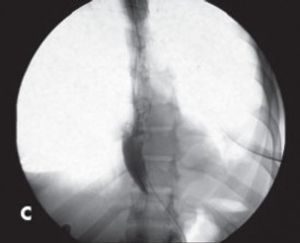

The development of a standardized treatment that simultaneously addresses achalasia and obesity is becoming more imperative as obesity becomes epidemic in the US. Here’s a case in point.